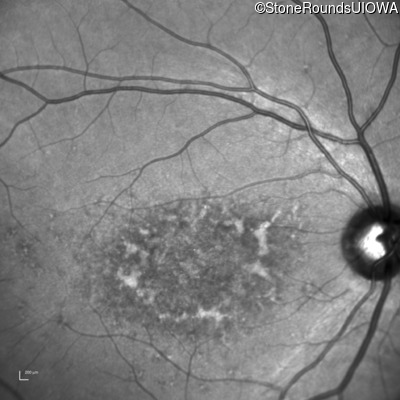

AR Stargardt Disease (IIA)

Age at visit: 22 years

This 22 year old woman first had difficulty seeing the blackboard at age 14 and this was not correctable with glasses.